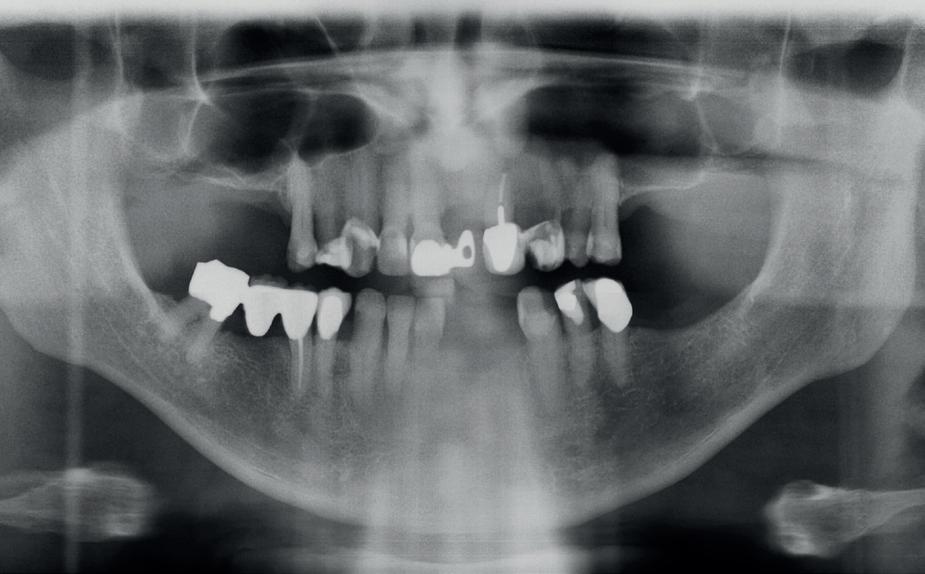

Diagnostische fase en infectiecontrole

De patiënt werd in de eerste fase gezien door de parodontoloog, implantoloog en restauratief behandelaar. Klinisch werden drie complicerende factoren vastgesteld: inadequate mondhygiëne, een ongunstige occlusale relatie en restauraties met gebrekkige marginale adaptatie met overhang. De patiënt werd opgenomen in het parodontale behandelprotocol.

De diagnose luidde lokaal parodontitis met ernstige furcatie aandoeningen; Stadium IV (vergevorderd); graad C (snel progressief) (afbeelding 7) De elementen die niet te behouden waren, werden geëxtraheerd.

Tijdelijke voorzieningen werden getroffen in de vorm van een etsbrug in de bovenkaak en een uitneembare voorziening voor de onderkaak.

Na afronding van de eerste twee behandelstappen werd parodontale stabiliteit bereikt, zoals waarneembaar op de parodontiumstatus en (röntgen)foto’s (afbeelding 6, 8). De patiënt toonde aantoonbare verbetering in mondhygiëne (afbeelding 4) en bleef gemotiveerd om de behandeling voort te zetten.

5. OPT intake